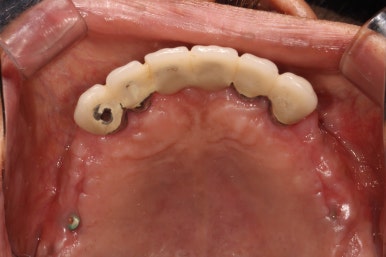

위턱 교합면에서도,

아래턱 교합면에서도 아주 정갈하고 깔끔하게 임플란트 크라운이 잘 제작된 것을 보실 수 있습니다.

사실 어디하나 흠잡을데 없다고 생각합니다....호호...